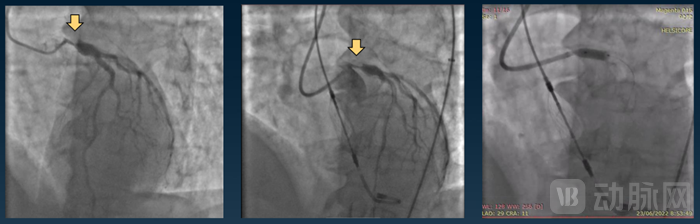

Magenta现已成功完成了首次人体研究,并于2022年将成果公布在心血管研究基金会(CRF)的经导管心血管治疗(TCT)年度科学研讨会。

据悉,Elevate™已可在患有血栓的患者动脉内安全、精准的部署以及脱鞘。其次,对于冠状动脉供血不足引发的静息性心绞痛(Rest Angina Prior),Elevate™可在患者进行高危PCI手术之前,为其进行多次持续有效的左主干动脉扩张治疗。

Elevate™扩张治疗

图源:TCT官网

血流动力学数据